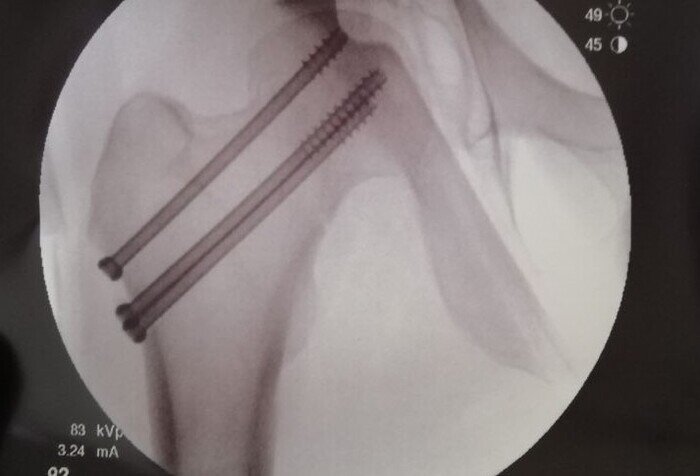

Жила-была нога. В детстве она любила играть в футбол, прыгать с трамплина на лыжах, ходить в зал и еще много разного. С возрастом все это осталось в прошлом, но она обзавелась новыми увлечениями - сплав по рекам, походы в горах, сквош. Больше всего нога любила кататься на горных лыжах. А самым любимым местом у нее были Доломитовые Альпы. Вот именно там, в уже далеком январе 2020 года, на крутом и жестком склоне она нашла себе приключения. Результатом достаточного легкого контакта с посторонними ногами стал прекрасный полет над склоном, но крыльев у ноги не было, поэтому летела она быстро, но недолго. Несмотря на то, что скорость на взлете была не самой большой, если верить трекеру в кармане, 69 км/ч, после приземления случилось следующее:

Уже через день стало так: